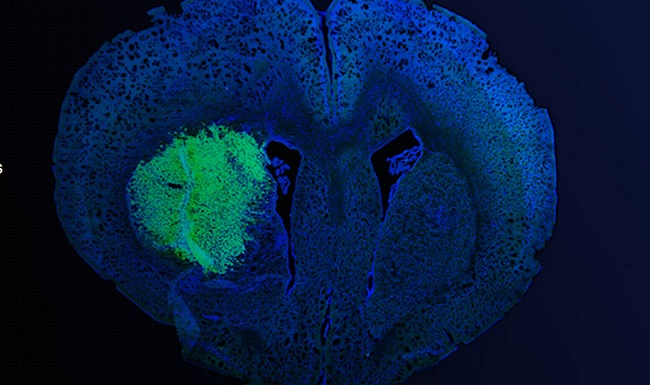

The Science Of Sprouting New Blood Vessels

Biologists have discovered a key regulator of blood vessel formation in both normal and cancerous cells.